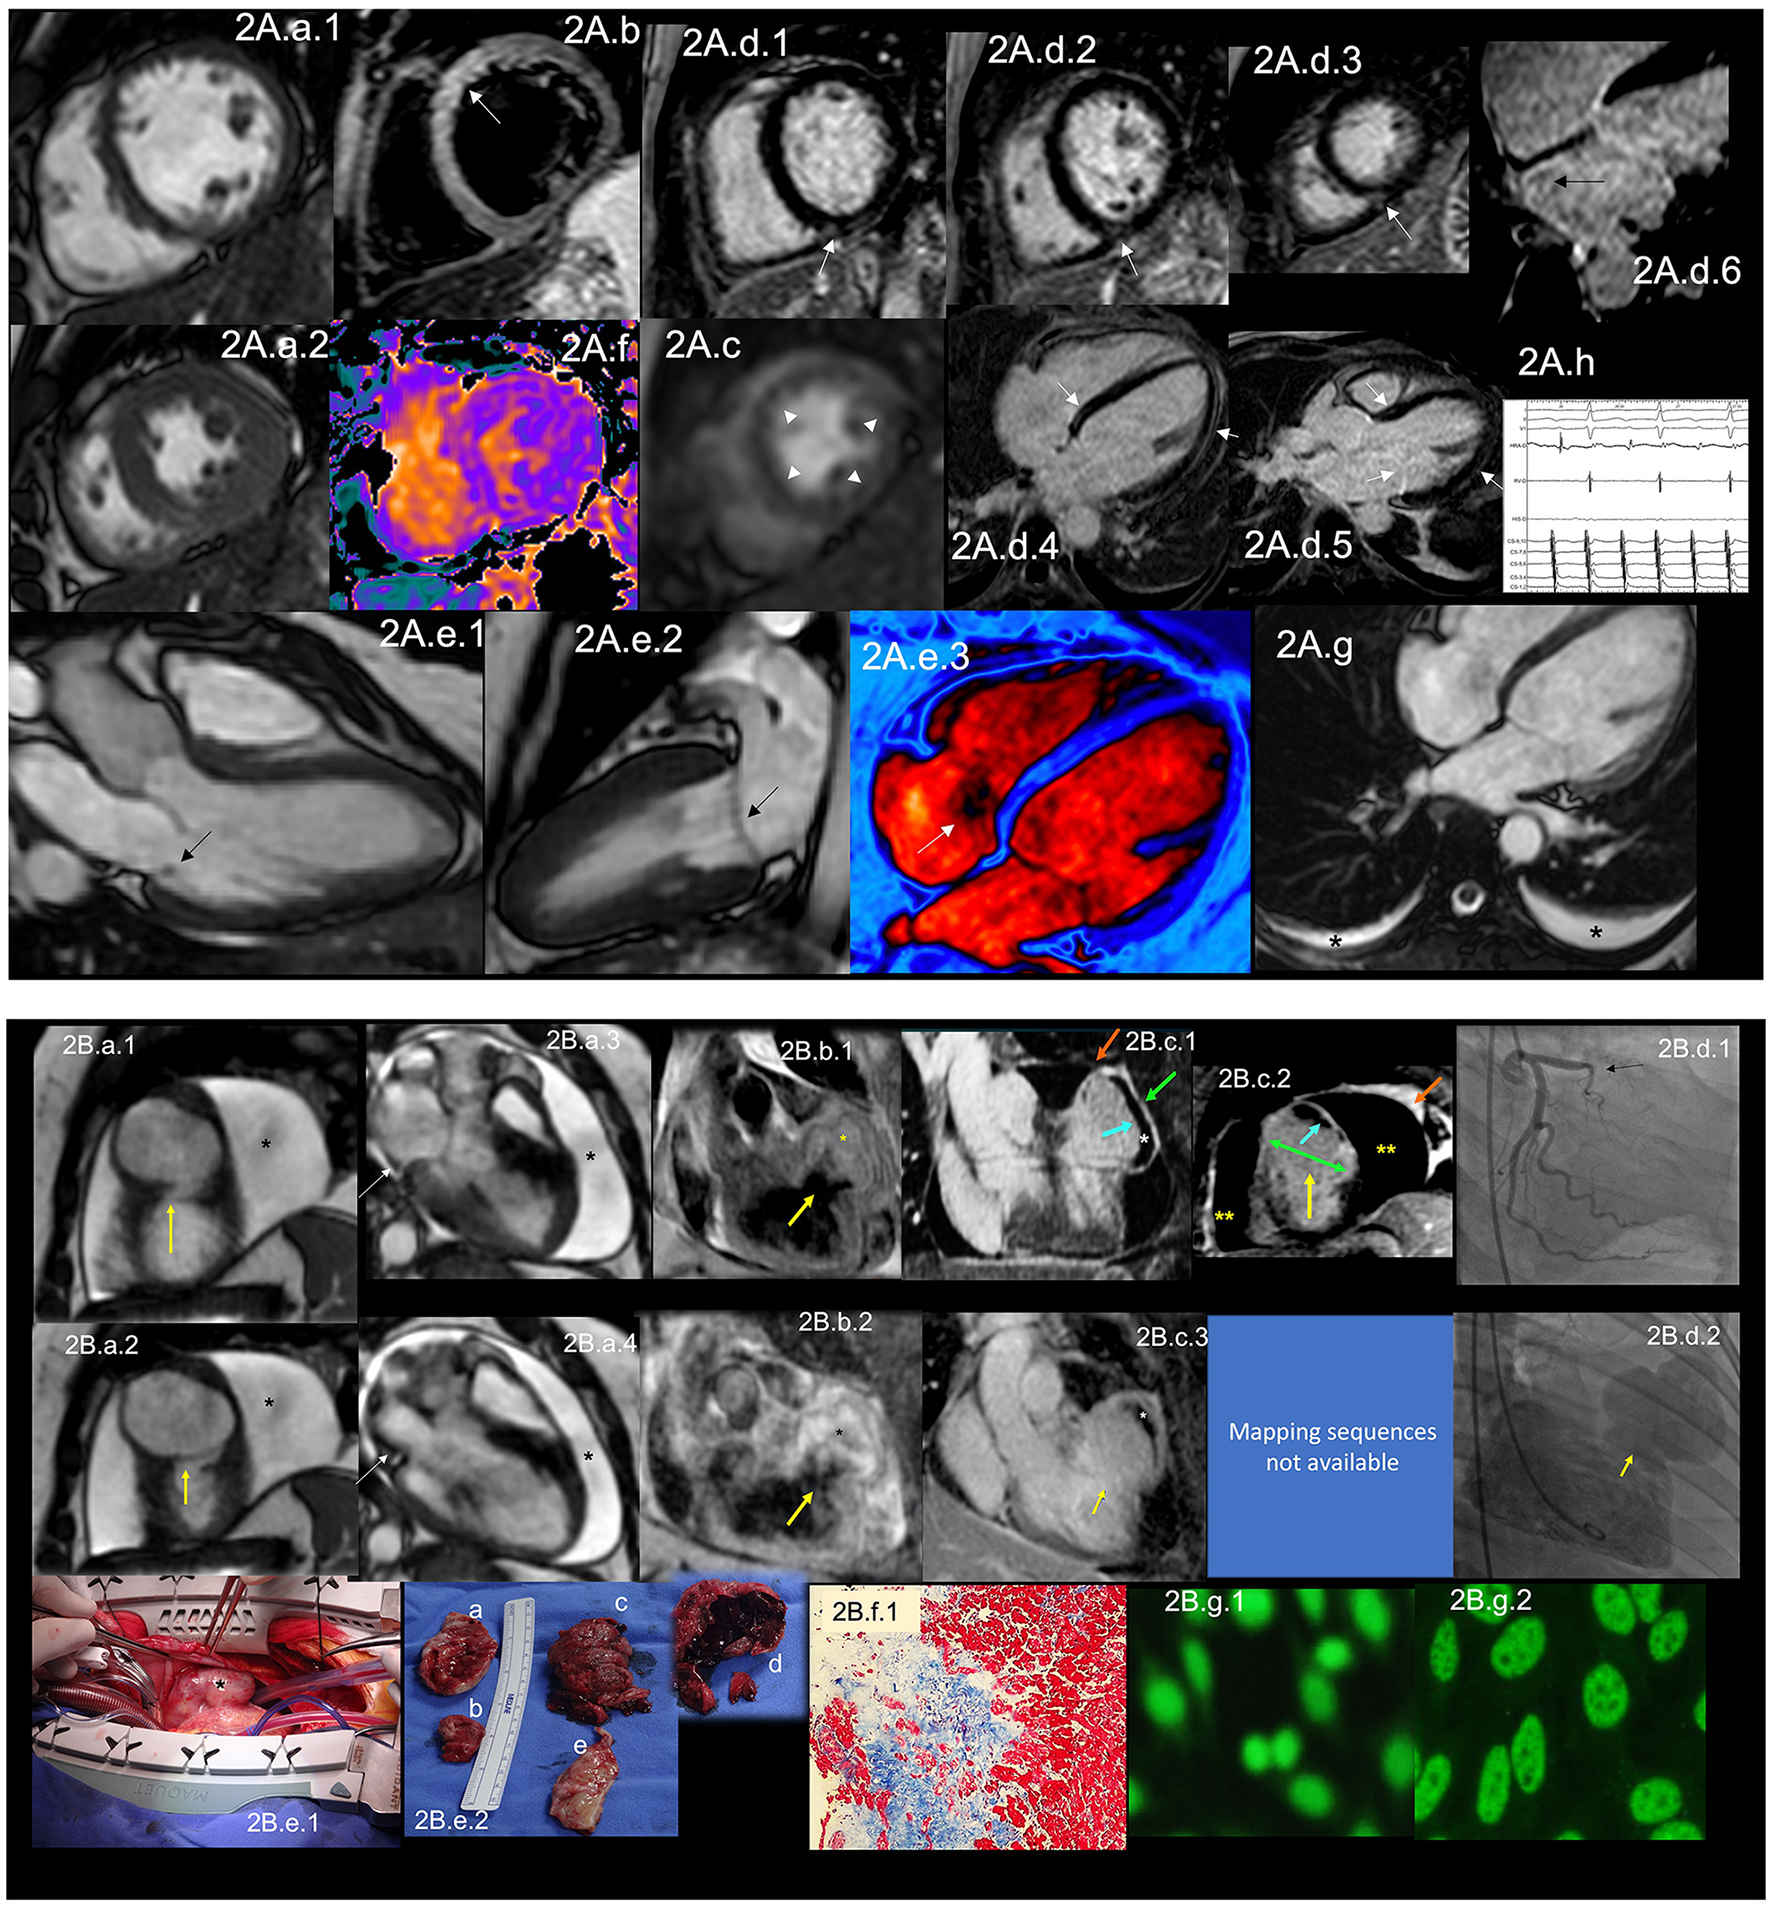

Figure 2

(A) CMR findings in SLE—(A) from an arrhythmic perspective. A panel figure demonstrates the array of findings from a comprehensive CMR study in SLE from an arrhythmia perspective. (A.a) Shows normal global and regional right and left ventricular functions in SSFP sequence still cine images in short-axis views at the mid-ventricular level in end-diastole (A.a.1) and end-systole (A.a.2) LVEF 66% and RVEF 63%. (A.b) T2-W STIR sequence in short-axis view projection at a mid-ventricular level demonstrating mildly increased signal intensity in the anterior, anteroseptal, and inferoseptal segments (arrow) with a myocardial/skeletal muscle ratio of 2.8 and (A.f) a color-coded T2 mapping (native T2 value of 48 ms) consistent with myocardial edema. (A.c) Stress CMR with FPP T1-W sequence with adenosine infusion at 140 mcg/kg/min over 6 minutes shows a subendocardial ring perfusion defect (arrowheads) consistent with subendocardial ischemia due to endothelial dysfunction and probably microvascular disease (no obstructive coronary artery disease in CCTA). (A.d.1) LGE PSIR sequence. (A.d.1–3) short-axis views at basal (A.d.1), mid (A.d.2) and apical (A.d.3) levels, and long-axis views in 4-chambers (A.d.4,6) and 3-chambers (A.d.5) projections. The arrows in these images show areas of focal fibrosis in the subepicardium in the inferior segments in (A.d.1–3) from the base to the apex. (A.d.4,5) shows areas of midventricular LGE in basal anteroseptal and inferoseptal segments (arrows) and subepicardial enhancement in mid and apical inferolateral segments (arrow). (A.d.6) A zoomed image of the 4-chambers view showing LGE suggestive of LA fibrosis (arrow). (A.h) A polygraphic trace of an EP study showing atrial fibrillation successfully ablated. (A.e.1–3) SSFP sequence still cine images in long-axis views, showing in a 3-chambers view an isointense, small nodule, in the ventricular side of the mitral valve suggestive of Libman-Sacks endocarditis (arrow) (confirmed by echo) (A.e.1), in a 2-chambers view, a mildly thickened mitral valve (A.e.2) and in a color-coded 4-chambers (A.e.3) the presence of tricuspid regurgitation (arrow). (A.g) An SSFP sequence still cine images in true axial view showing bilateral pleural effusion (asterisks). SLE, systemic lupus erythematosus; CMR, cardiovascular magnetic resonance; SSFP, steady-state free precession; LVEF%, left ventricular ejection fraction; RVEF%, right ventricular ejection fraction; T2-W STIR, T2-weighted short-tau inversion recovery; FPP, first-pass perfusion; T1-W, T1-weighted; CCTA, invasive coronary angiography; LGE, late gadolinium enhancement; PSIR, phase-sensitive inversion recovery; LA, contrast enhancement magnetic resonance angiography; EP, electrophysiology. (B) CMR findings in SLE—(B), from a thrombotic perspective. A panel figure demonstrates the array of findings from a comprehensive CMR study in a 1.5 T scanner of SLE from a coronary thrombosis perspective. (B.a.1–4) SSFP sequence still cine images in short-axis views at mid to apical ventricular level in end-diastole (A.a.1) and end-systole (A.a.2) and long-axis 3-chambers view, in end-diastole (B.a.3) and end-systole (B.a.4) that shows in (A.a.1) the loss of continuity of the LV anterior segment (yellow arrow), with normal thickening of the remaining segments (B.a.2) surrounded by a large pericardial effusion (black asterixis), that exhibits hemodynamic compromise as the diastolic collapse of the LA [yellow arrow in (B.a.3,4)]. LVEF 42% and RVEF 65%. (B.b,c) Show the tissue characterization findings. (B.b.1) T1-W sequence in long-axis view demonstrating a wide-necked outpouching of the LV anterior wall with the apparent loss of myocardial continuity with a thinned out, fibrosed muscle surrounding the cavity consistent with true aneurysm (yellow arrow) with tissue within the aneurysmal cavity of two different intensities (yellow asterisks) suggestive of thrombus. (B.b.2) T2-W STIR sequence in long-axis view confirming the findings of T1-W sequences (yellow arrow) with the evident different signal intensity of the tissue components inside the aneurysmal cavity (black asterixis) suggestive of two varying ages of the thrombus, recent and old, and slow-flowing blood. (B.c) LGE PSIR sequence. (B.d.1) Long-axis 3-chambers view showing loss of myocardial continuity, a large cavity surrounded by scarred myocardium (green arrow) with a large thrombus on its endocardial aspect (white asterisks), pericardial enhancement (orange arrow), and a large pericardial effusion (yellow double asterisks) that are confirmed on the corresponding short-axis view (B.c.2). (B.c.3) A long TI LGE-PSIR long-axis 3-chambers view confirming previous data and showing the new thrombus component (yellow asterisks). (B.d.1) An invasive angiography demonstrating a total occlusion of the proximal LAD (arrow) and the invasive ventriculography (B.d.2) Showing a large leak of contrast media at an anterior mid-ventricular level impossible to differentiate aneurysm from pseudoaneurysm. (B.e.1) Open heart surgery showing the intact LV wall covered by the pericardium consistent with a true aneurysm (arrow) which was successfully resected (B.e.2), and surgery confirmed CMR findings, a ventricular aneurysm (B.e.2.a,b), a transmural scar (B.e.2.e) and a large thrombus (B.e.2.c) composed of two different aged thrombi (B.e.2.d). H.E. stain histology confirmed the presence of a large scar with no evidence of atherosclerosis (B.f.1). Based on the inflammatory component of the pericardium, suspicion of autoimmune instead of atherosclerotic etiology was suspected and confirmed by the finding of ANA with a homogeneous pattern in the pericardial effusion (B.g.1) and peripheral blood of a fine speckled pattern (B.g.2). SLE, systemic lupus erythematosus; CMR, cardiovascular magnetic resonance; SSFP, steady-state free precession; LVEF%, left ventricular ejection fraction; RVEF%, right ventricular ejection fraction; LV, left ventricle; LA, left atrium; T2-W STIR, T2-weighted short-tau inversion recovery; FPP, first-pass perfusion; T1-W, T1-weighted; ICA, invasive coronary angiography; LGE, late gadolinium enhancement; PSIR, phase-sensitive inversion recovery; TI, time to inversion; LAD, left anterior descending artery; H.E., hematoxylin and eosin.

Clinical Manifestations of CV Involvement and Pathogenesis of Cardiac Manifestations

The most common CV manifestation is pericarditis presenting with pericardial effusion, which can occur in 11–54% of cases (39) during the disease (Figure 2A.a.1,2,2B.a.1–4,c.1–3). Even though it is the most common CV manifestation, cardiac tamponade rarely develops. It is associated with positive antinuclear antibodies (ANA), fever, and chest pain, just as acute viral pericarditis, so excluding other causes of pericardial disease in these patients is mandatory. Still, in disease activity, pericarditis is rarely due to other etiologies (39).

Valvular heart disease in SLE involves more than Libman-Sacks endocarditis (Figure 2A.e.1). Valve thickening (Figure 2A.e.2) and valvular dysfunction (Figure 2A.e.3) can also occur (45). In a study, Vivero et al. included 211 patients with SLE. Of those, 53 had significant valvular involvement; however, they found no valve vegetations in any of these patients (46). In a meta-analysis by Hussain et al., they included 2556 SLE patients. The most commonly involved was the mitral valve, with mitral regurgitation being the most common valve disease. Other lesions were mitral stenosis, tricuspid regurgitation (Figure 2A.e.3), and aortic regurgitation (47). In the same study, the authors found that compared to control subjects, SLE patients had an increased risk of developing valve disease, the highest risk being valvular thickening (RR 6.99, CI 3.64–13.44) and valvular vegetations (RR 7.73, CI 3.09–19.3) (47). VHD has been linked to high titers of antiphospholipid antibodies (aPL) (48, 49).

Specific manifestations can cause HF in SLE, which has been reported with a prevalence of 1–10% in SLE (47, 50). MI and coronary artery disease (CAD) are the leading causes of CVD in these patients (Figure 2B), besides being significant risk factors for the development of HF (50). Treatment of SLE with disease modifier drugs such as corticosteroids or hydroxychloroquine is further associated with increased CV risk (35) related to dose-dependent cardiotoxicity and resultant manifestations of restrictive cardiomyopathy (51). Dhakal et al. described risk factors associated with HF development in SLE. Traditional risk factors such as smoking, obesity, hypertension, CAD, advanced age, and male sex play a role in HF development, but also there are disease-specific risk factors such as left ventricular hypertrophy, described in as much as 20% of cases, myocarditis, chronic kidney disease, and vasculitis, among others (50). Primary myocardial involvement manifested as myocarditis affects ~3–9% of SLE patients (Figure 2A.b,d.1–5,f), while African-Americans are at higher risk (39).

Regarding the pathophysiology of CV manifestations in SLE, there is a role of immune complexes in CV manifestations of SLE. In pericarditis, for example, granular depositions of immunoglobulins and C3 complement have been found in pericardial tissue, and neutrophil predominance in pericardial fluid exudate, ANA (Figure 2B.g.1,2), and other autoantibodies can be found (39).

Endothelial dysfunction (Figure 2A.c) is accepted as the central hypothesis of CVD, especially CAD, in SLE patients. The mechanism by which this occurs is complex. Roughly, endothelial dysfunction is caused by several pathways, including expression of vascular cell adhesion molecules, which correlates with higher coronary artery calcium scores (53), activation of type I interferon and IFN-α, which inhibit eNOS expression at protein and mRNA levels which impair insulin-mediated nitric oxide production in endothelial cells (54). Cellular mediators for endothelial dysfunction involve low-density granulocytes which form neutrophil extracellular traps that promote vascular leakage and activate the B-catenin signaling pathway (38). Conversely, T cells play a proatherogenic role through their migration to the arterial wall (55). Mercurio et al. reported increased radial artery stiffness, increased aortic pulse pressure, and its correlation with some inflammatory markers such as C-reactive protein (CRP) and erythrocyte sedimentation rate (ESR), but not with disease activity in 43 SLE patients. The authors concluded that inflammation is the primary determinant of CV complications in SLE (56).

MI is mainly due to coronary atherosclerosis, but it might be due to acute in situ coronary thrombosis when there is an association with aPL (57). Arterial thrombosis manifests as coronary thrombosis in 23% (58) (Figure 2B.d.1,2). It has been described that MI secondary to coronary in situ thrombosis can be the first manifestation of SLE and APS which can be complicated by catastrophic APS (57) (Figure 2B). Treatment for STEMI in these patients must be as stipulated in current guidelines.

Although it is not the most common manifestation of SLE, serositis is one of the American College of Rheumatology (ACR) classification criteria to define the disease (59). Serositis can manifest as pleurisy (Figure 2A.g) with pleural effusion, which occurs in 15–34% (60), or as pericarditis with pericardial effusion, which is the most common CV manifestation and can occur in 11–54% of patients with SLE (39, 60), during the disease. A study of the Hopkins Lupus Cohort evaluated predictors of pleurisy and pericarditis among different populations. They found that African-American ethnicity, male gender, and serological markers such as ESR, Anti-DNA, and low C3/C4 were strong predictors for serositis in the form of pleurisy and/or pericarditis (60).

CMR Role

Autopsy studies in patients with SLE show cardiac involvement in up to 40% of patients, of which only 10% were clinically diagnosed (40). Even though echocardiography is the leading non-invasive imaging modality in the initial evaluation of CVD, it might not be the appropriate initial modality in SLE patients since it is not ideal for tissue characterization. Mavrogeni et al. analyzed patients referred to evaluate typical and atypical cardiac symptoms with normal Echo and connective tissue diseases. They found that 25.2% of these patients had myocardial fibrosis. When the percentage of LV mass with late gadolinium enhancement (LGE) exceeded 5%, they were at increased risk of future cardiac events (61). Burkard et al. evaluated 30 SLE patients, mainly female, with no history of CAD and found that 43% (n = 13) had abnormal CMR; the main findings were the presence of LGE (Figure 2A.d.1–5,B.c.1–3), stress perfusion abnormalities (Figure 2A.c), and pericardial effusion (Figure 2B) (40). This reinforces the need for early CMR evaluation in these patients mainly for (1) detection of acute disease that cannot be diagnosed with Echo (e.g., arterial wall inflammation, asymptomatic myocardial involvement). (2) Evaluation of CAD with CMR perfusion techniques in patients with high CV risk-stratified with novel tools. (3) Evaluation of pericardial tissue. (4) Evaluation of valve involvement and (5) early initiation of cardiac protective treatment in patients with detected myocardial involvement, considered a risk factor for HF in these patients (62–64). See Table 2 for detailed CMR offerings to SLE and Table 1 for pros and con over other imaging modalities.